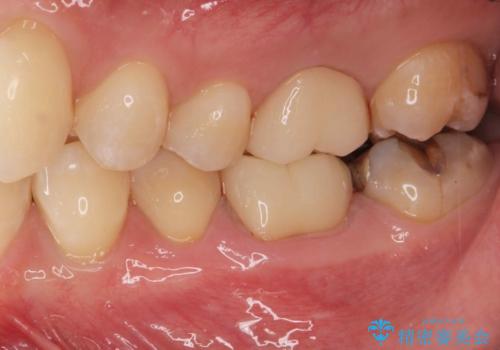

不十分な根管治療も精密根管再治療を行ったのち、精度の高いジルコニアセラミッククラウンで食べ物の詰まらない歯の形態へと改善していきます。

食事のたびに感じていた煩わしい思いから解放され、また大きく目立っていた銀歯も審美的に白く改善し満足いただくことができました。